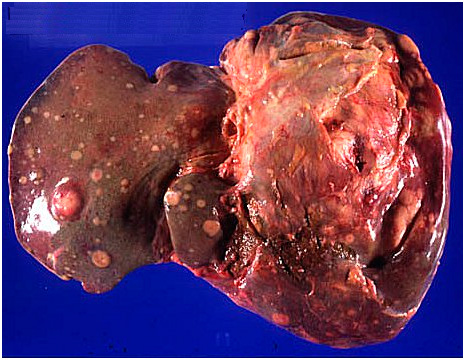

Основная причина возникновения метастазов в железе — это высокая кровоснабжаемость печени. Орган получает большое количество крови из воротной вены и создает условия для захвата раковых клеток из кишечника, желудка, легких или молочных желез.

Кроме того, анатомическое расположение железы делает ее уязвимой. Печень находится рядом с множеством других органов, что облегчает попадание недуга через лимфатическую систему или кровь.

- Высокая кровоснабжаемость. Печень получает большой объем крови из воротной вены, которая несет кровь из всех органов. Это обеспечивает прямой доступ для раковых клеток к органу.

- Анатомическое расположение. Железа находится в брюшной полости, рядом с множеством других органов, что облегчает распространение раковых клеток в него через лимфатическую систему.

- Функции печени. Орган выполняет важные функции: обработка веществ, фильтрацию крови и выделение желчи. Это делает его активным центром метаболизма и местом, где раковые клетки находят условия для роста и развития.